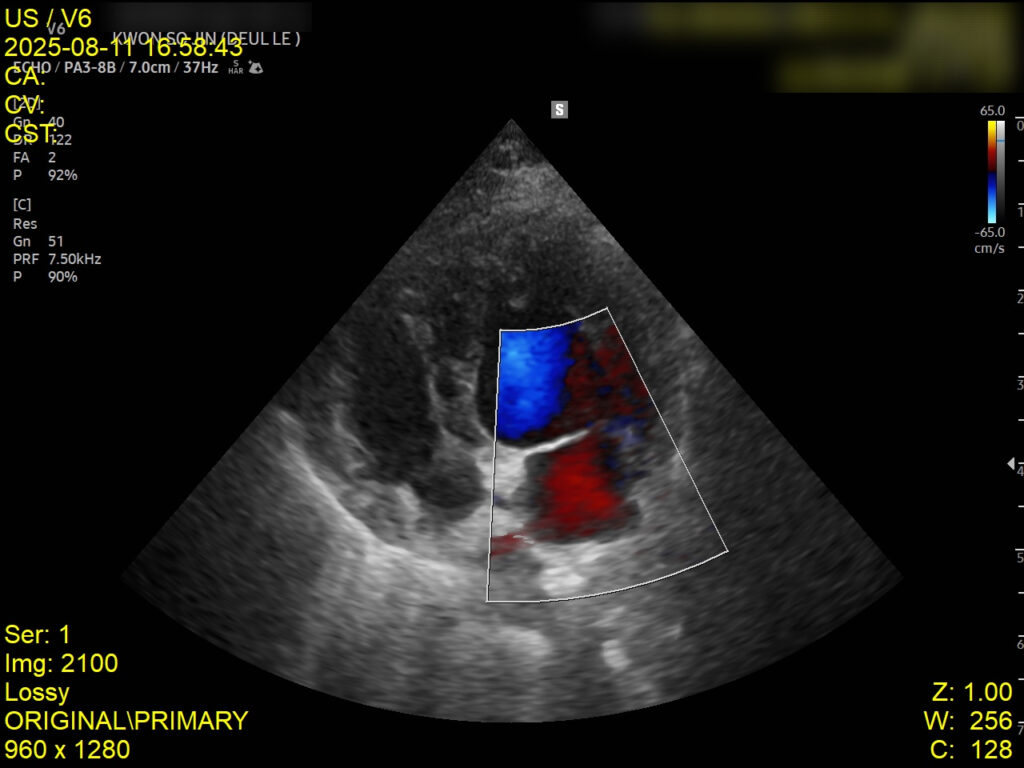

4. 심장초음파 검사

심장초음파에서는 좌심부전 소견은 없었으나, 폐성고혈압이 확인되어 이에 대한 약물 치료가 병행되었습니다. 이는 호흡곤란의 주 원인이 심장이 아닌 폐 자체의 염증성 병변임을 뒷받침하는 결과입니다.

심장초음파 검사 사진 / 출처: 강서 YD동물의료센터